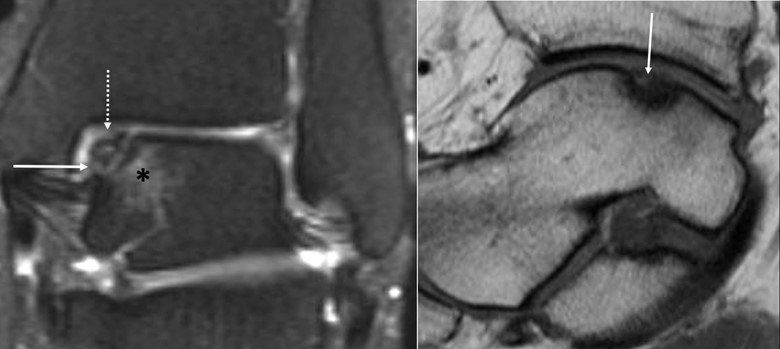

When an ossific fragment is not displaced, as in this case of a 39-year-old who twisted her ankle on the stairs 6 months ago, MRI can be helpful to evaluate for stability. On the coronal T2 fat-suppressed image—left image above—we can see that the fragment is somewhat irregular at the articular surface, but there is fluid signal intensity completely undercutting the fragment (solid arrow), and bone marrow edema in the adjacent talus, suggesting that the fragment is unstable [5]. There is mild subchondral bony irregularity and depression (dashed arrow), too. Other signs of instability may be cystic change or partial or complete separation of the fragment from the donor site [8].

The sagittal T1 image—right image above—shows that a large portion of the fragment is low in signal intensity, which persists on all sequences, and there is articular surface collapse, suggesting that the portion is at least partially osteonecrotic [8]. Another portion still demonstrates fat signal intensity (solid arrow) on T1 and high signal on the T2 fat-suppressed image, suggesting that tis portion remains viable.